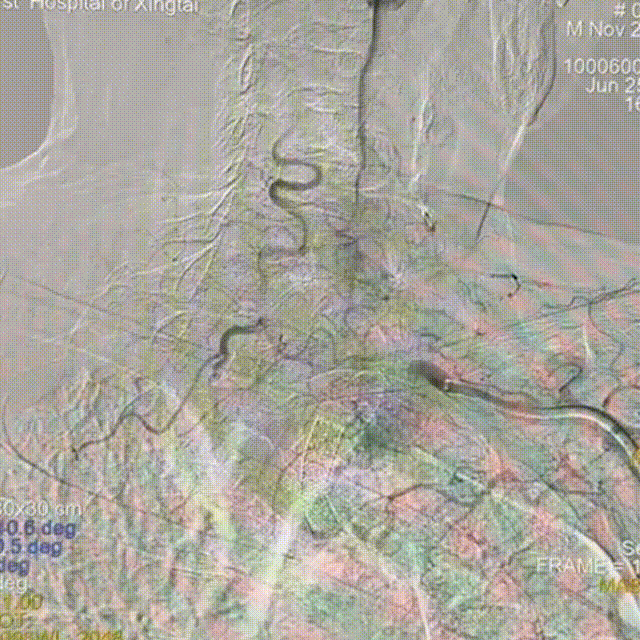

术前影像学检查结果

左侧锁骨下动脉重度狭窄。

左侧锁骨下动脉盗血。